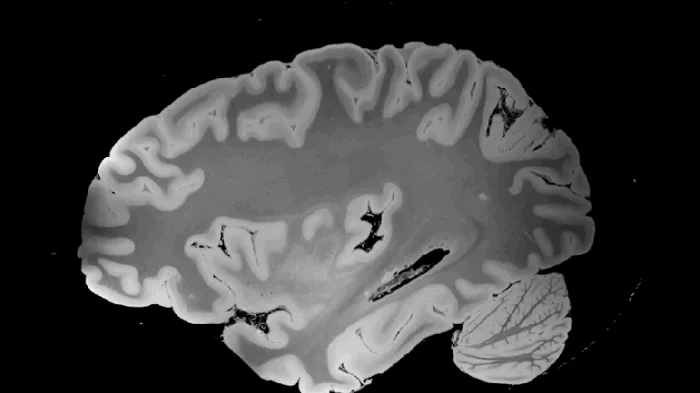

Они взяли мозг 58-летней женщины, скончавшейся в отделении реанимации, без истории психических и неврологических заболеваний. Два года он пролежал в консервации, а затем его поместили в специальный сфероидальный чехол, чтобы исключить малейшие движения и удалить пузырьки воздуха. И отправили в сканер.

Но не в обычный, а в 7-тесловый монстр. Для сравнения: стандартные больничные МРТ работают на 1,5–3 Тесла. А тут — 70 000 гаусс, мощнейшее магнитное поле, способное вытянуть из тканей детали, недоступные при жизни.

Сканирование длилось почти пять дней. 100 часов 8 минут чистого времени, 7,92 терабайта необработанных данных. Итог — трёхмерная карта мозга с изотропным разрешением 100 микрометров. То есть можно разглядеть объекты меньше 0,1 миллиметра.

Что это даёт? На снимках видна миндалина (центр страха и эмоций) в таких подробностях, которые раньше были доступны только под микроскопом после вскрытия. Можно отследить тончайшие изменения в анатомии, которые при жизни могли влиять на память, принятие решений, тревожность.